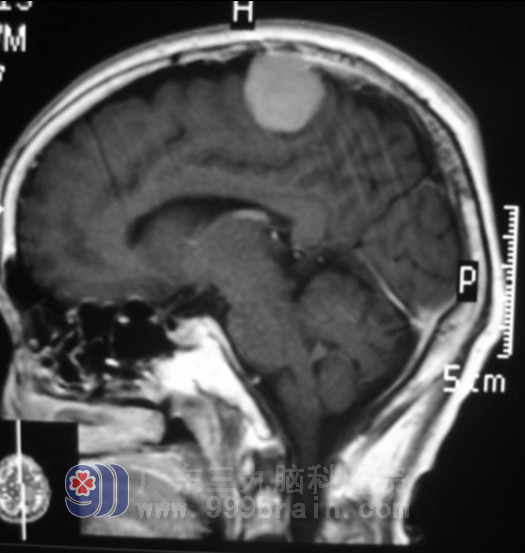

入院后,完善相关检查,头颅MR检查示“左顶部占位,直径约3cm,考虑脑膜瘤可能”。初步诊断:左顶叶占位病变(脑膜瘤可能性大)。广东三九脑科医院神经外五科 鲁明主任查看后,凭借着多年的临床经验,指示完善术前相关检查,择期手术治疗。入院第五天鲁明主任为张阿姨在全麻下行“左侧额顶镰窦旁脑膜瘤切除术”。术中见肿瘤明显侵犯硬膜,并部分侵犯上矢状窦,肿瘤质中,灰白色,边界清,予显微镜下连同受侵犯硬膜一起完整切除,术后予以抗炎止血等治疗。术后随访:张阿姨身体恢复得很好,头晕症状消失了。”http://www.999brain.com

▲术前